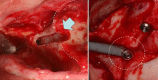

Results: The lack of maxillary boney support at the implant platform resulted in significant higher stress measured within the zygoma implant as well as the zygoma bone.

Conclusion: The maxilla is the primary support when zygoma implants are placed under functional loads. Quad-cortical stabilization of the zygoma implants and their cross-arch stabilization are recommended to reduce the degree of stress whenever possible.